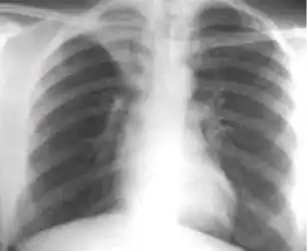

Normal findings

These are films that are completely normal, with no identifiable cardiothoracic or musculoskeletal abnormality.